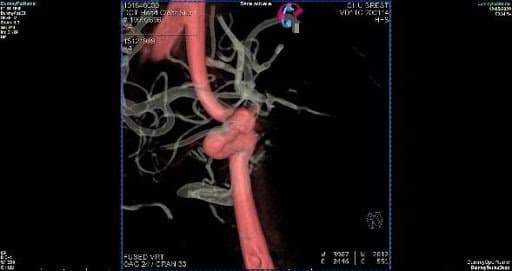

Confrontation imagerie Modèle 3D vs Patient

En effet, la superposition des images médicales du modèle 3D et de l’anévrisme d’un patient, démontre la précision obtenue.